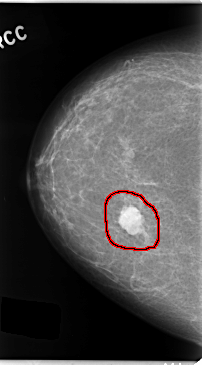

ics_version 1.0 filename C-0131-1 DATE_OF_STUDY 22 9 1995 PATIENT_AGE 48 FILM FILM_TYPE REGULAR DENSITY 1 DATE_DIGITIZED 16 1 1998 DIGITIZER LUMISYS LASER SEQUENCE LEFT_CC LINES 4776 PIXELS_PER_LINE 2712 BITS_PER_PIXEL 12 RESOLUTION 50 NON_OVERLAY LEFT_MLO LINES 4696 PIXELS_PER_LINE 2760 BITS_PER_PIXEL 12 RESOLUTION 50 NON_OVERLAY RIGHT_CC LINES 4736 PIXELS_PER_LINE 2616 BITS_PER_PIXEL 12 RESOLUTION 50 OVERLAY RIGHT_MLO LINES 4704 PIXELS_PER_LINE 2720 BITS_PER_PIXEL 12 RESOLUTION 50 OVERLAY |

FILE: C_0131_1.RIGHT_CC.OVERLAY TOTAL_ABNORMALITIES 1 ABNORMALITY 1 LESION_TYPE MASS SHAPE LOBULATED MARGINS CIRCUMSCRIBED ASSESSMENT 5 SUBTLETY 5 PATHOLOGY MALIGNANT TOTAL_OUTLINES 1 BOUNDARY |